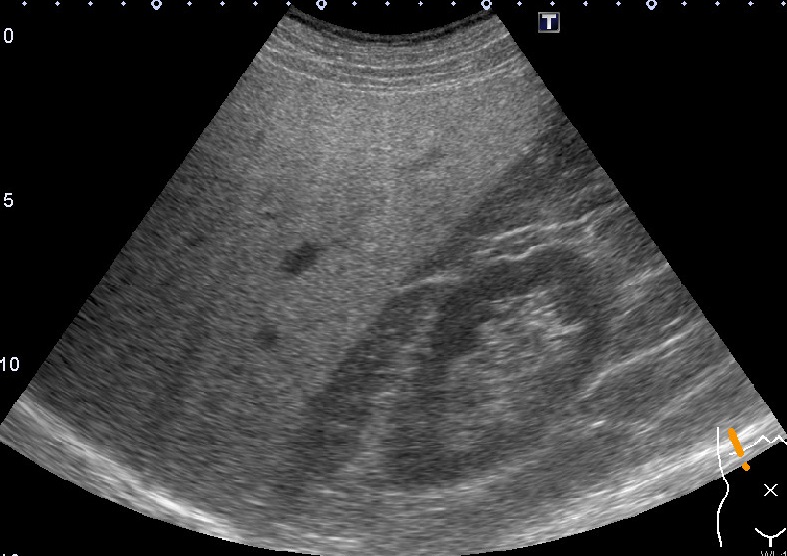

超音波検査では通常の腹部検査に加えFibroScanによる肝硬度が評価可能です。FibroScanはプローブからせん断波を発振し伝搬する速度を計測します。せん断波は肝臓が硬ければ早く伝搬し軟らかければゆっくりと伝搬する性質があります。また同時に肝臓の脂肪量も評価でき肝硬変だけでなく脂肪肝や非アルコール性脂肪肝炎(NASH)などの診断にも有用です。

上腹部超音波+肝硬度測定

非アルコール性脂肪肝炎(NASH)症例